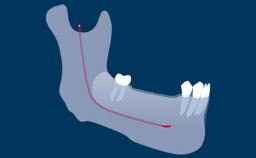

Radiography plays an important role in implant dentistry.

These investigations are used to assist in the diagnosis of pathology, aid in implant treatment planning, and monitor peri-implant bone levels on maintenance assessments, such as this image taken at a 1-year follow-up visit.

- interpret linear measurements in 2D and 3D imaging, and translate them into the specific clinical situation